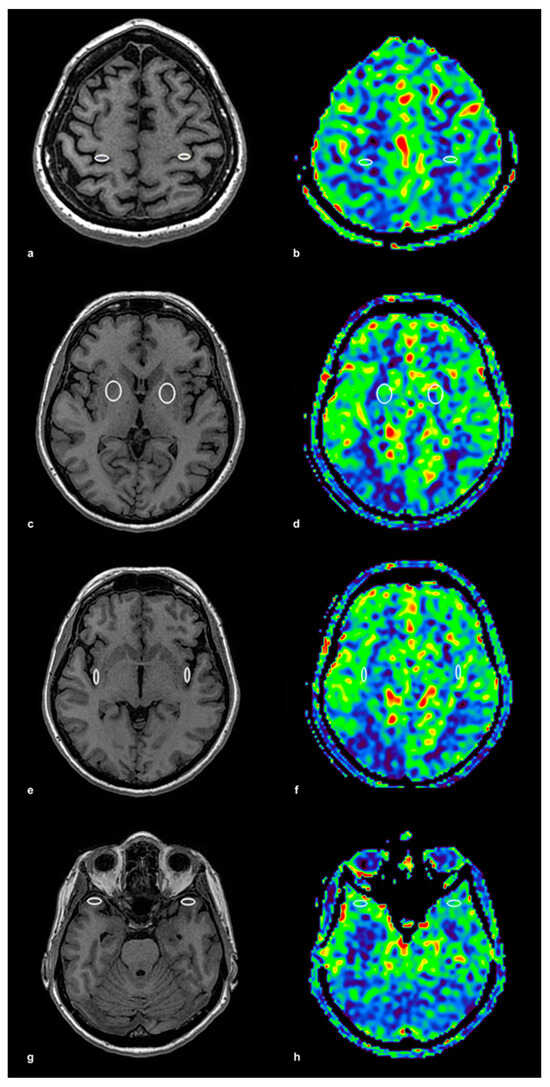

The ROIs were initially placed on high-resolution 3D T1-weighted anatomical images, ensuring precise localization within the gray matter, and then automatically transferred to the corresponding ASL perfusion maps acquired with identical geometric parameters. This method ensured accurate spatial alignment between anatomical and perfusion imaging. The ROI placement procedure is illustrated in Figure 1, using a control subject to demonstrate anatomical accuracy and spatial consistency. In panel (a), bilateral ROIs were positioned within the precentral gyrus on T1-weighted anatomical images, while panel (b) shows the corresponding ASL perfusion map with these ROIs overlaid for CBF quantification. Panels (c,d) depict the lentiform nucleus, again with paired anatomical and perfusion images. The same approach was applied to the insular cortex (e,f) and the temporal cortex (g,h), ensuring consistent methodology across all examined brain regions. To illustrate the same ROI protocol in a patient with significant unilateral carotid artery stenosis, Figure 2 presents corresponding anatomical and perfusion images. As in the control example, ROIs were bilaterally placed in the precentral gyrus, lentiform nucleus, insular cortex, and temporal cortex. Panel (a) shows ROI localization on T1-weighted images for the precentral gyrus, and panel (b) displays the matching ASL perfusion map. Panels (c,d) represent the lentiform nucleus, (e,f) the insular cortex, and (g) and (h) the temporal cortex, with anatomical and perfusion images paired in each case. This consistent ROI placement ensured reproducibility of the analysis and facilitated accurate intergroup comparisons of regional CBF values. ROI sizes ranged from 15 to 40 mm2, depending on the anatomical region, individual morphological variation, and the presence of age-related brain atrophy. Elliptical ROIs were applied to thinner cortical structures, such as the insular and precentral cortices, while circular ROIs were used in larger subcortical areas, including the lentiform nucleus and temporal cortex. This adjustment provided robust and anatomically valid perfusion estimates across the study population.

Figure 1. ROI Placement and ASL Perfusion Map in a Control Subject. This figure illustrates the placement of regions of interest (ROIs) on T1-weighted anatomical images and their corresponding arterial spin labeling (ASL) perfusion maps in a control subject. (a) T1-weighted image with ROI placement in the precentral gyrus (frontal cortex) bilaterally, ensuring precise localization in the gray matter, and (b) the corresponding ASL perfusion map with identically positioned ROIs for cerebral blood flow (CBF) quantification. (c) T1-weighted image with ROI placement in the lentiform nucleus bilaterally, and (d) the corresponding ASL perfusion map. (e) T1-weighted image with ROI placement in the insular cortex bilaterally, and (f) the corresponding ASL perfusion map. (g) T1-weighted image with ROI placement in the temporal cortex bilaterally, and (h) the corresponding ASL perfusion map. ROI sizes ranged from 15 to 40 mm2, with elliptical ROIs used in thinner cortical regions and circular ROIs in larger areas. The colored ASL perfusion maps (b,d,f,h) represent quantitatively measured cerebral blood flow (CBF), with warmer colors (red, yellow) corresponding to higher CBF values and cooler colors (green, blue) indicating lower values.